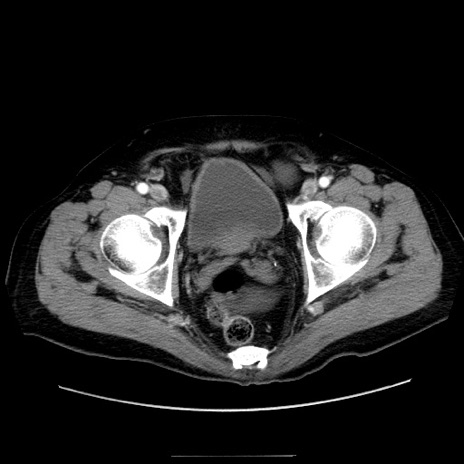

症例30(横断像)

【症例】80歳代男性

【現病歴】約6時間前から臍下部痛が出現。次第に腹部膨隆・背部痛も生じてきたため来院。背部痛の場所は変化しない。

【身体所見】意識清明、BT 36.3℃、BP  131/87mmHg、P 87bpm、SpO2 100%(RA)、臍周囲自発痛・圧痛あり、反跳痛なし、自発痛部位に一致して板状硬あり、腹部膨隆、腸雑音減弱、CVA tenderness両側陰性。